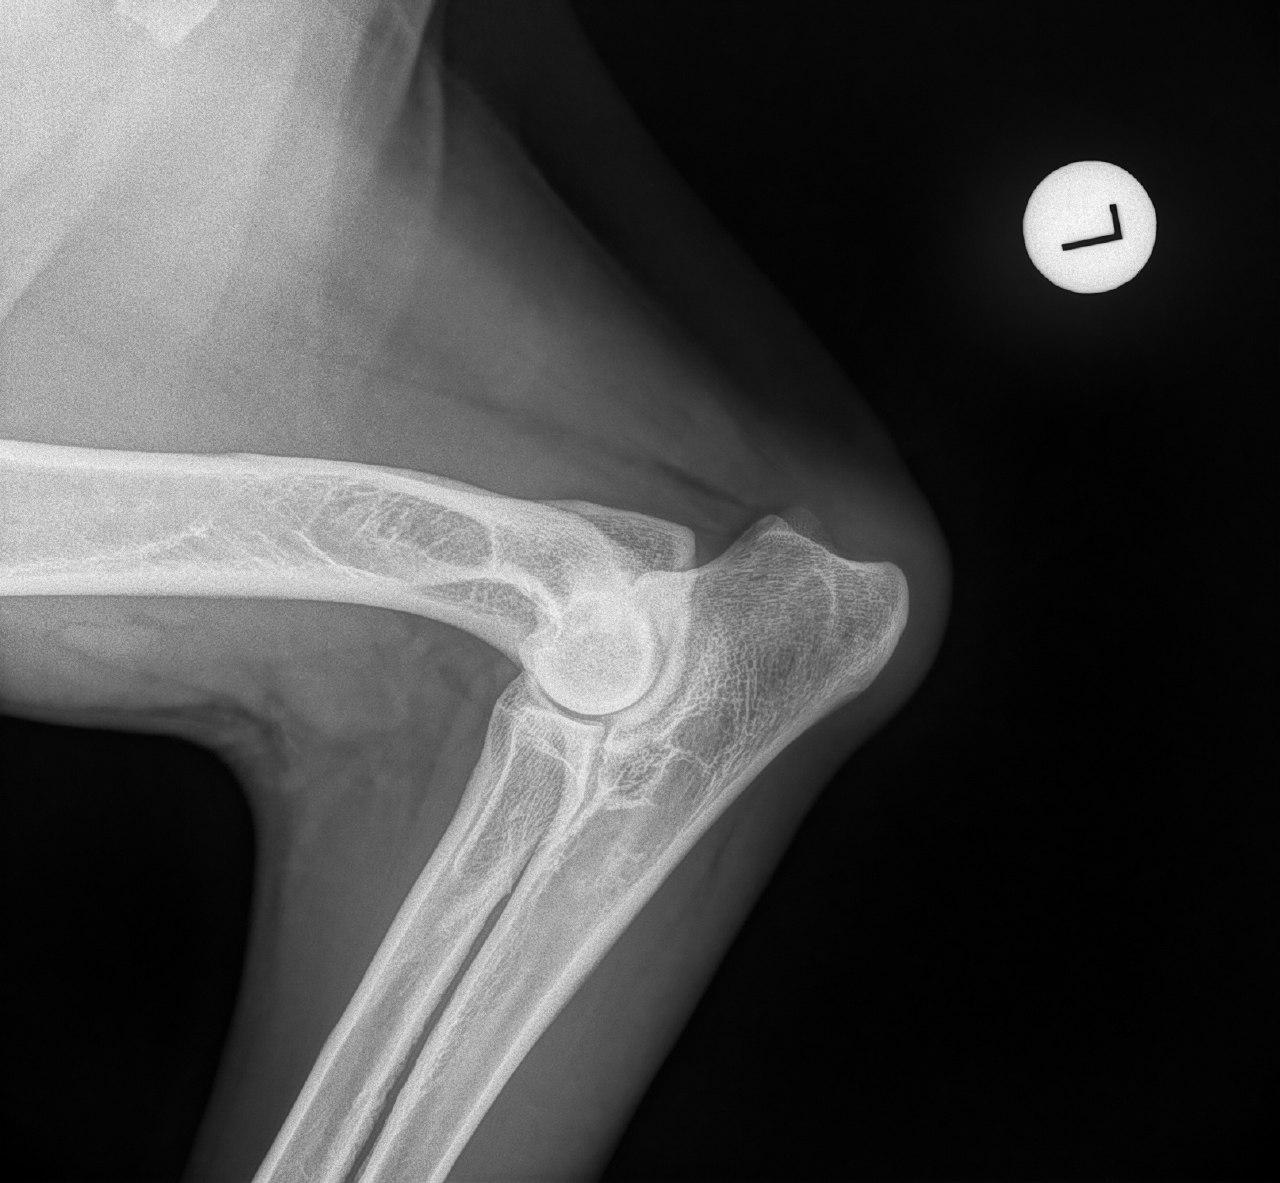

Mit der HD ist das so ne Sache..... die Vererbung spielt eine sehr große Rolle, ja. Aber bei unserer Peggy Zb ist es so, dass mehrere Generationen nachweislich HD und ED frei sind und auch frei von Spondylosen. Als einziger Hund überhaupt in der gesamten Zucht hat unsere Dame alles mitgenommen, was zu kriegen war;(: sie hat nicht nur schwere HD, weil ihre Hüfte viel zu locker ist, sondern dadurch bedingt am rechten Knie bereits schwere Arthrose und hinten links eine Sehenschwäche (durch Überlastung), weshalb sie dort durchtrittig ist. Und als würde das alles nicht schon vollkommen reichen, wurden aktuell auch noch mehrere heftige Spondylosen diagnostiziert;(. An einer Stelle ist sogar schon etwas abgebrochen8|.

Meiner hat schwere ed rechts...im Stammbaum gibt es lediglich einmal beim Opa "ed fast normal " und trotzdem hat er sie.